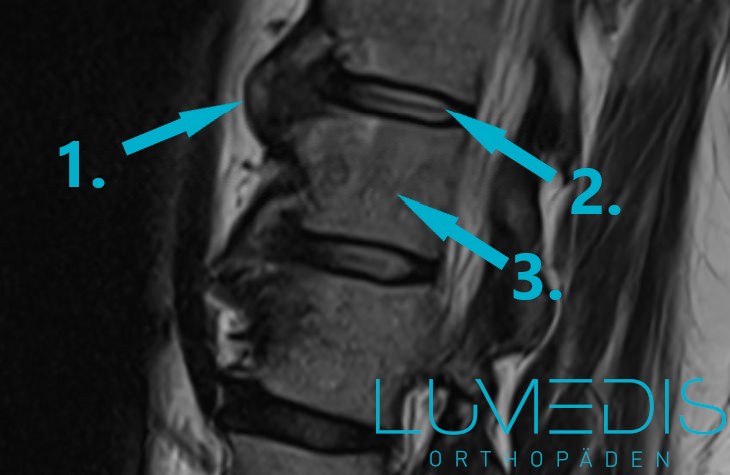

MRT der LWS (T2, seitlich)

Abbildung eines Bandscheibenvorfalls